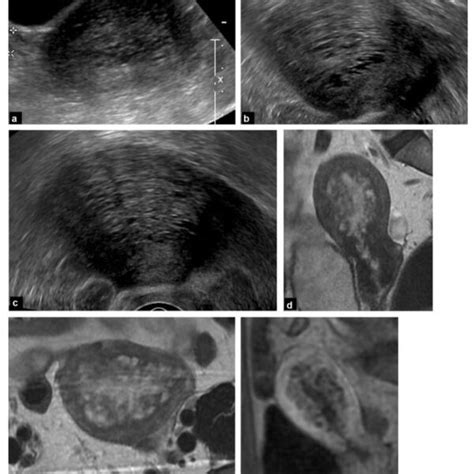

- Ecografía Transvaginal (ETV): Actualmente, la ETV es considerada el método diagnóstico de primera línea debido a su alta sensibilidad, especificidad, bajo costo y disponibilidad. Permite visualizar el útero con detalle, identificando características como:

- Engrosamiento asimétrico de la pared uterina.

- Quistes miometriales (áreas anecoicas de 2-8 mm).

- Islas hiperecoicas o líneas y brotes subendometriales ecogénicos.

- Sombreado en forma de abanico.

- Útero globuloso.

- Vascularidad translesional aumentada con Doppler color.

- Zona de unión irregular o interrumpida.

- Resonancia Magnética (RM): La RM es un método muy preciso y no invasivo, con alta sensibilidad y especificidad para la detección de adenomiosis. Las secuencias en T2 y los cortes sagitales son particularmente útiles para evaluar la anatomía uterina, especialmente la zona de unión (junctional zone - JZ). Los hallazgos característicos en RM incluyen:

- Engrosamiento focal o difuso de la zona de unión (mayor a 12 mm).

- Pequeñas imágenes redondeadas, hiperintensas en T2, dentro de la zona de unión.

- Áreas de baja intensidad de señal que corresponden a hiperplasia del músculo liso.

- Focos brillantes en T1, indicativos de hemorragia.

- Pobre definición de los bordes entre el miometrio normal y anormal.